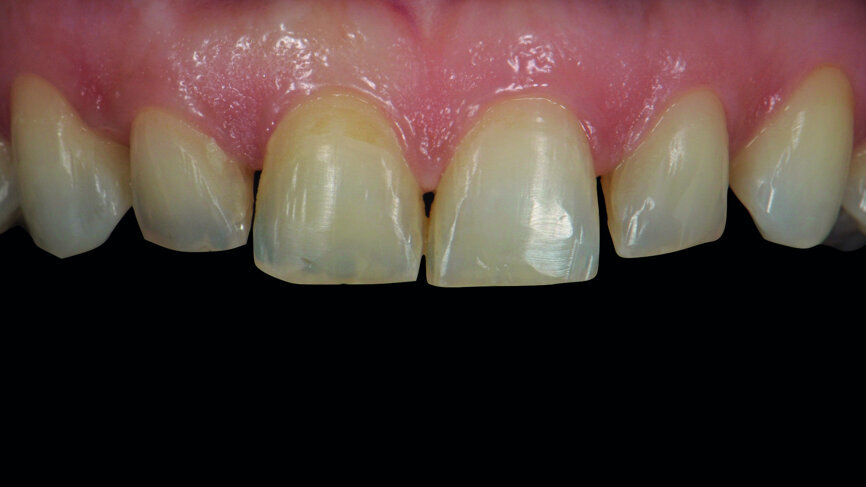

Fig. 1: Initial photograph of the anterior teeth prior to orthodontic treatment.

A 35-year-old patient presented at the office with the chief desire that the aesthetics in the anterior region be changed (Fig. 1). A diagnostic wax-up was performed, followed by mock-up fabrication, in order to obtain a preliminary visualisation of the final outcome. Orthodontic treatment was proposed in order to align the teeth in a more favourable position for veneers requiring minimal preparation and to reduce the overbite. One year after treatment, the patient returned for the final prosthetic rehabilitation (Figs. 2a & b).